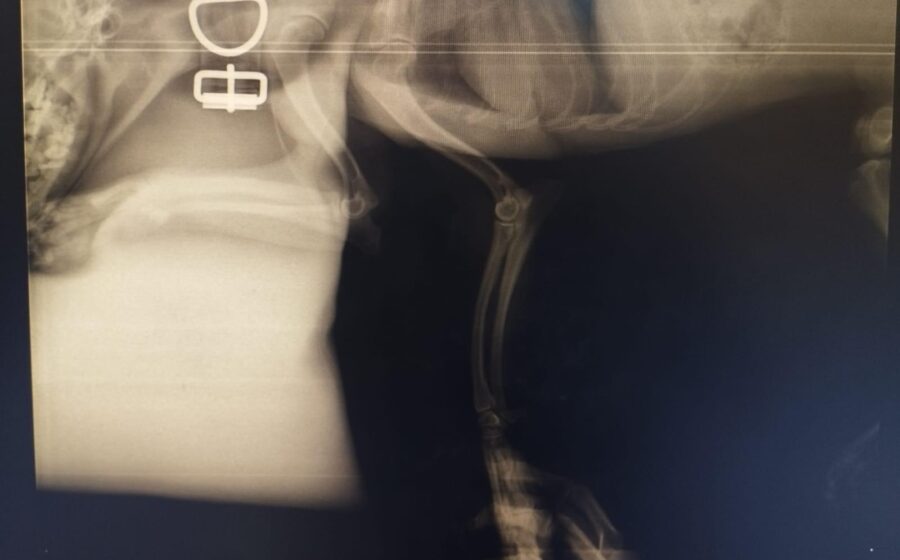

Er hat bereits eine Operation am Bein hinter sich. Doch ein neues Röntgenbild zeigt, dass leider auch seine andere Hüfte gebrochen ist. Eine zweite Operation ist daher notwendig. Danach benötigt er eine spezielle physiotherapeutische Betreuung, um wieder vollständig auf die Beine zu kommen. Er ist ein Kämpfer und hat es so sehr verdient, endlich schmerzfrei zu leben.